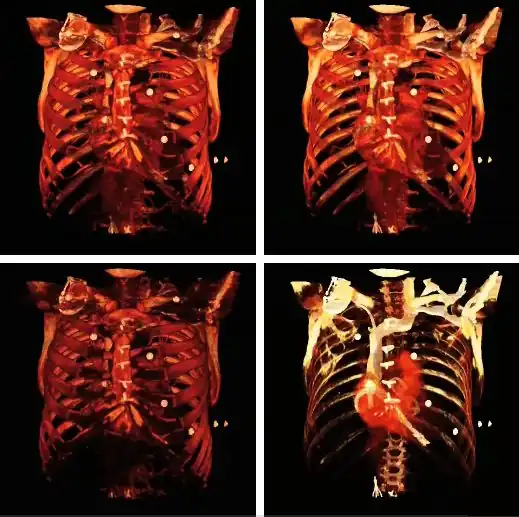

3D VR contrast enhancement progressively applied, from top left to bottom right panels, through the voxel value range.

Note also that the colour look-up table (CLUT) can be varied to highlight features of particular interest, as shown in the set of images below:

3D volume renderings using four different CLUTs.